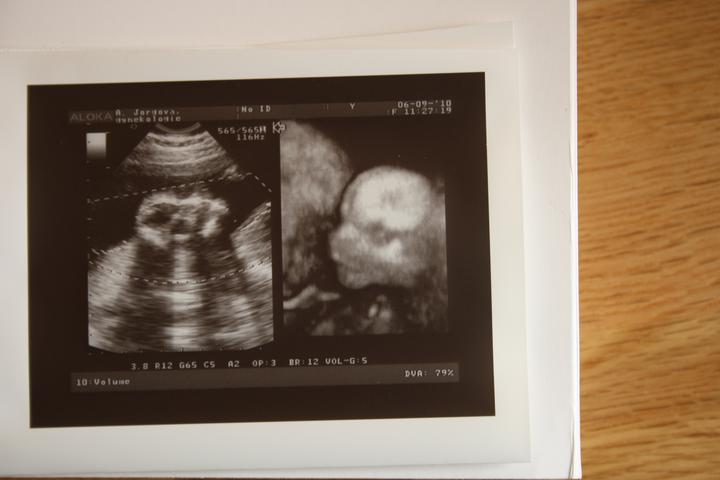

tak srdíčko se dneska krásně třepotalo 🙂